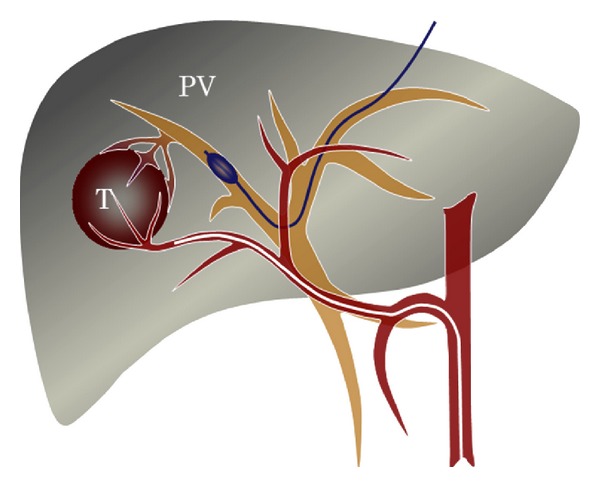

Хирургические процессы при эмболизации гемангиомы на фото

Раздел: Снимки-откровения